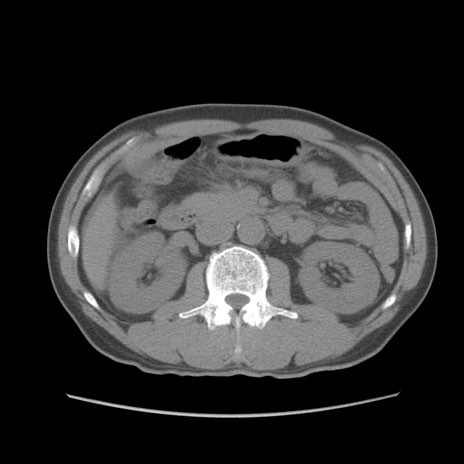

症例56 CT(横断像)

脂肪ウインドウ